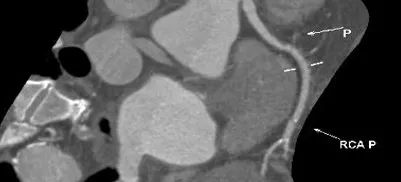

四、CT评估

1.术前冠状动脉影像学评估:冠状动脉轻度粥样硬化累及多支,前降支中度狭窄,回旋支及右冠轻度狭窄。

4 心脏角度 约68°,呈横位+升主扩张

5入路评估 整体直径较大,但存在多处扭曲(胸主动脉+腹主动脉+主动脉弓+右侧股动脉)

患者为三叶瓣,瓣叶增厚,极重度钙化,左冠窦可见柱状钙化延申至流出道,双冠脉风险高度尚可,瓣叶未见冗长,考虑冠脉风险较低,心脏角度约68°,呈横位+升主扩张,预备上Snare;收缩期左室测值较小且流出道短径约16.8mm,选择20球囊预扩,预装L26 Venus-A瓣膜。

入路选择:整体直径较大,但存在多处扭曲(胸主动脉+腹主动脉+主动脉弓+右侧股动脉),考虑腹主动脉扭曲可大鞘拉直,胸主动脉扭曲可能影响手术操作,选择右股动脉作为主入路。